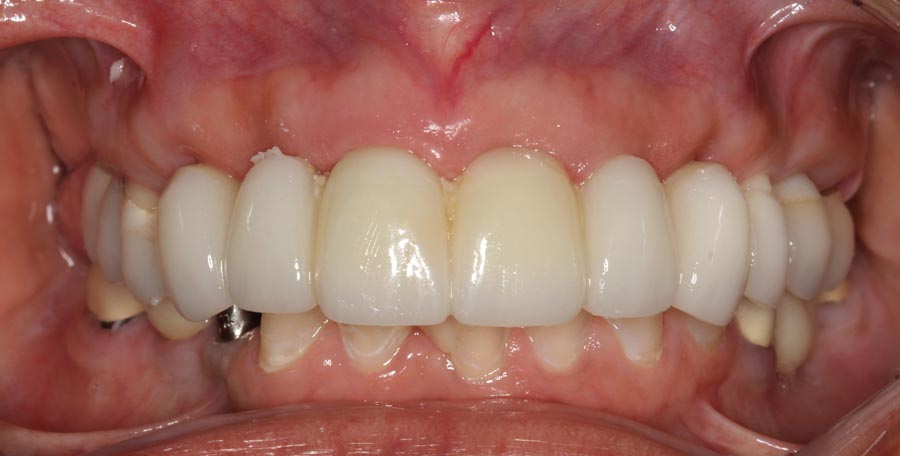

Smile GalleryImplant RestorationsFull Mouth Implant Restoration Full arch zirconia implant bridge (full smile) 1 of 37 Pre-op full smile Pre-op lips retracted Pre-op panoramic x-ray Extraction of strategic teeth Placement of implants Extraction of some remaining teeth after verification of adequate implant stability Occlusal view Post-op panoramic x-ray Immediately fabricated provisional restoration (tissue side view) Immediately fabricated provisional restoration (occlusal side view) Immediate provisional delivered on day of surgery Immediate provisional 2 weeks later Scalloped tissue developed from the provisional at 2 weeks Jig used for making a master impression Provisional in place (full smile) Provisional in place (lips retracted) Provisional in place (right side) Provisional in place (left side) Wax try-in (full smile) Wax try-in (right side full smile) Wax try-in (left side full smile) Wax try-in (full face, lips together) Wax try-in (full smile) Wax try-in (right side) Wax try-in (left side) Wax try-in (lips retracted) Full arch zirconia implant bridge on master cast (frontal view) Full arch zirconia implant bridge on master cast (occlusal view) Implant positions and soft tissue representation on master cast (occlusal view) Soft tissue representation on master cast (frontal view) Full arch zirconia implant bridge (tissue side view) Soft tissues on day of delivery (occlusal view) Soft tissues on day of delivery (frontal view) Full arch zirconia implant bridge delivered (lips retracted) Full arch zirconia implant bridge (lips retracted, close up) Post treatment panoramic x-ray Full arch zirconia implant bridge (full smile)